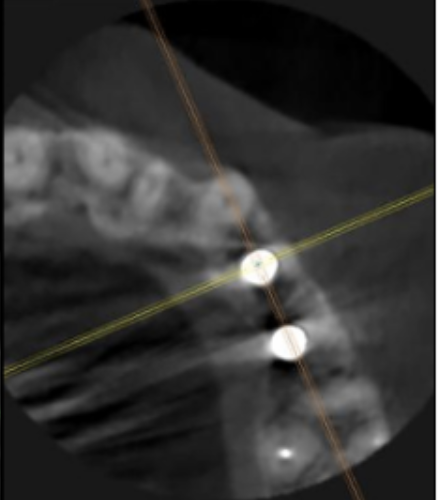

インプラント埋入前のCTによる確認